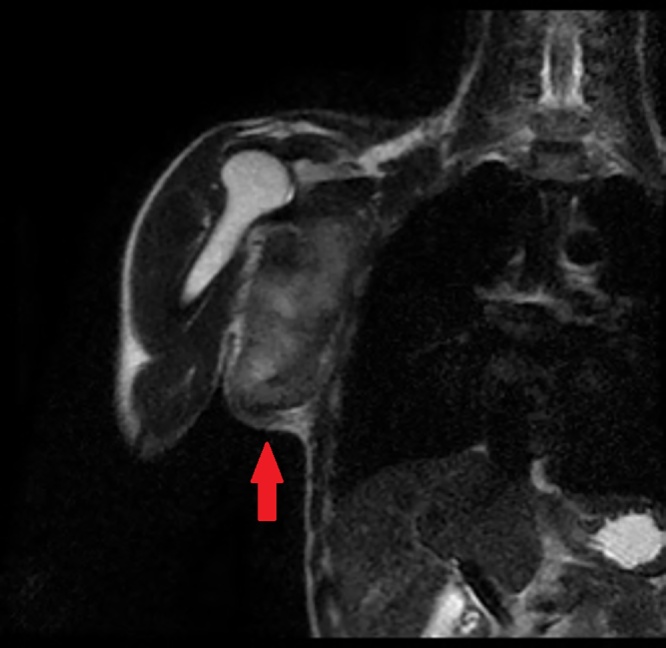

A 27-year-old male came to our hospital with complaints of a swelling in the right axilla for 2 and ½ years. It was insidious in onset and progressive in nature. The patient denied any history of pain, trauma, fever or weight loss. On examination, the swelling measured 12 cm × 10 cm, extending to the lateral border of the right scapula posteriorly, to the chest wall medially, to the apex of the axilla superiorly and to the 6th intercostal space inferiorly (Fig. 1). There was no warmth or tenderness noted. Skin over the swelling was normal and the surface was nodular. Dilated blood vessels were present over the surface of the swelling (Fig. 2). There were no visible pulsations, no discharge and no scars or sinuses. Movement of the shoulder joint was normal. The swelling was hard in consistency and not mobile. There were no palpable axillary or cervical lymph nodes. Baseline blood investigations were normal. Chest X-ray was normal and showed no osteolytic lesions of the right ribs or scapula (Fig. 3). Magnetic Resonance Imaging was done and showed an irregular mass in the right axilla in the muscular- subcutaneous plane measuring 10.8 × 8.8 × 12 cm. This mass was attached to the lateral border of scapula (Fig. 4) and displaced the subscapularis anteriorly. The infraspinatus, teres minor and teres major muscles were displaced posteriorly (Fig. 5). The lesion appeared iso to hyperintense to muscle on T1 and heterogeneously hyperintense on T2-weighted images. Multiple scattered areas of hemorrhage were noted within. The neurovascular bundle was seen displaced cranially. The lesion abutted the median, radial, ulnar nerves and axillary vessels in few sections. The lesion abutted the serratus anterior on the medial aspect.

Fig. 4.

MRI showing an irregular mass in the musculo-subcutaneous plane.